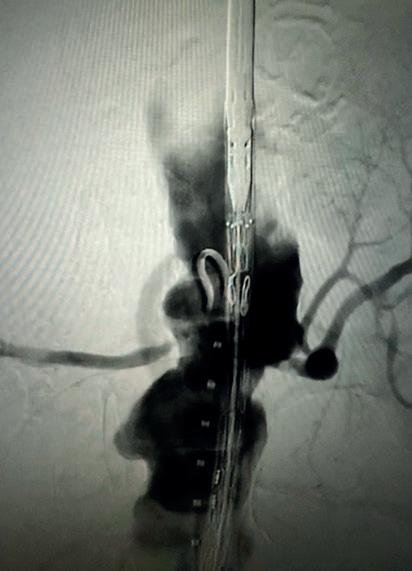

low threshold for further interventions “crucial” following rescue of prior EVAR with PMEG

The findings of a recent study on reinterventions and sac dynamics after fenestrated endovascular aneurysm repair (FEVAR) with a physician-modified endograft (PMEG) for index aneurysm repair and following prior EVAR led researchers to conclude that “vigilant” surveillance and a low threshold for further interventions are “crucial” following PMEG for rescue of prior EVAR with loss of proximal seal.

NICHOLAS J SWERDLOW (Beth Israel Deaconess Medical Center, Boston, USA) shared these findings at VAM 2023 on behalf of senior author Marc L Schermerhorn (Beth Israel Deaconess Medical Center) and colleagues.

Swerdlow et al note in their study abstract that, while the high frequency of reinterventions after FEVAR with a PMEG has been well-studied, the impact of prior EVAR on reinterventions and sac behaviour following these procedures remains unknown. In the present study, therefore, the researchers analysed three-year rates of reinterventions and sac dynamics

following PMEG for index aneurysm repair compared with PMEG for prior EVAR with loss of proximal seal.

The investigators analysed 122 consecutive FEVARs with PMEGs at a tertiary care centre that was submitted to the US Food and Drug Administration (FDA) in support of an investigational device exemption (IDE) trial. They excluded patients with aortic dissection, type I–III thoracoabdominal aneurysms, non-elective procedures and prior aortic surgery other than EVAR, for a final cohort of 92 patients.

Patients were divided into those who underwent PMEG for index aneurysm

repair (index-PMEG) and those who underwent PMEG for rescue of prior EVAR with loss of proximal seal (rescue-PMEG).

Results

Swerdlow shared with the audience that, of the 92 patients included in the analysis, 55 (60%) underwent index-PMEG and 37 (40%) underwent rescue-PMEG. He added that rescuePMEG patients were older—78 years (interquartile range [IQR] 75–83) vs. 73 years (69–78), p<0.001. Otherwise, there were no statistically significant differences in baseline demographics and procedural characteristics.

The presenter reported that perioperative mortality was 1.8% for index-PMEG and 2.7% for rescuePMEG (p=0.8) and that, at three years, overall survival was 83% for indexPMEG and 72% for rescue-PMEG (p=0.08).

In addition, he noted that freedom from reintervention was significantly

higher for index-PMEG than rescuePMEG, specifically 79% vs. 45% at three years (p<0.001).

Swerdlow then shared sac dynamic findings. He revealed that, at three years following index-PMEG, aneurysm diameter was stable in 58% of patients and decreased in 42% of patients, with no cases of sac expansion.

At three years following rescuePMEG, however, he noted that aneurysm diameter was stable in 31% of patients, decreased in 31% of patients and increased in 38% of patients (p=0.05).

Conclusions

The presenter stated in his conclusion that FEVAR with PMEGs for index aortic repair and rescue of prior EVAR with loss of proximal seal are “two distinctly different entities.”

He summarised that, following FEVAR with a PMEG for index aneurysm repair, less than a quarter of patients had undergone reintervention at three years and sac expansion was “rare”.

At three years following PMEG rescue of prior EVAR with loss of proximal seal, however, it was observed that over half of patients had undergone reintervention and over a third had ongoing sac expansion, which led Swerdlow to underscore the importance of “vigilant” surveillance and a low threshold for further interventions in this group of patients.